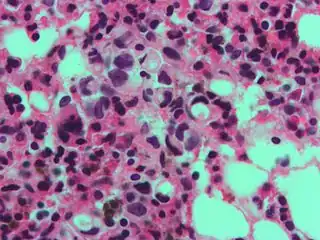

The name of the cell comes from its appearance; signet ring cells resemble signet rings. They contain a large amount of mucin, which pushes the nucleus to the cell periphery. The pool of mucin in a signet ring cell mimics the appearance of a finger hole and the nucleus mimics the appearance of the face of the ring in profile.

Gastric signet ring cell carcinoma. H&E stain.

High magnification micrograph showing signet ring cells, with clear cytoplasm, in metastatic breast carcinoma. H&E stain.